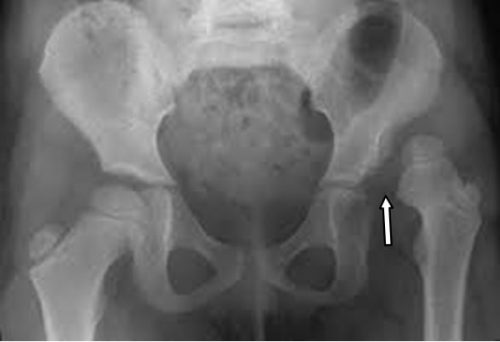

Chẩn đoán Khớp háng là Hỏi bệnh sử và khám thực thể. Việc chẩn đoán thường được xác nhận bằng chụp x-quang. Hình ảnh bổ sung với chụp cắt lớp vi tính hoặc chụp cộng hưởng từ có thể cần thiết.

Điều trị Khớp háng bao gồm nắn trật khớp hàng, phẫu thuật đặt lại khớp háng trật, phục hồi chức năng. Trật khớp háng có thể kèm liệt thần kinh mác hoặc thần kinh chày sau hoặc toàn bộ thần kinh hông to, do đó cần điều trị phục hồi chức năng trật khớp háng và điều trị các tổn thương thần kinh kèm theo.